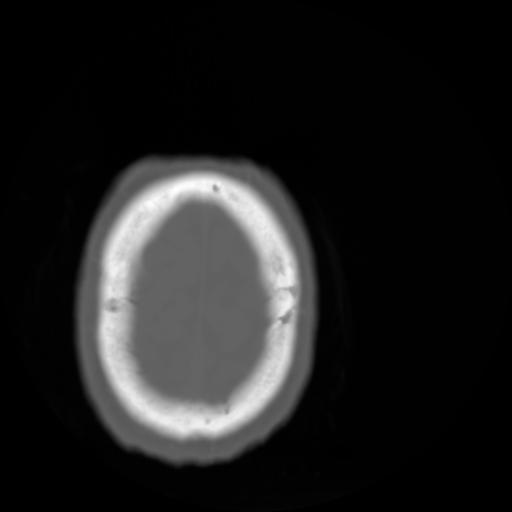

3 CEREBRO,,Axial,3.0,CEREBRO,,